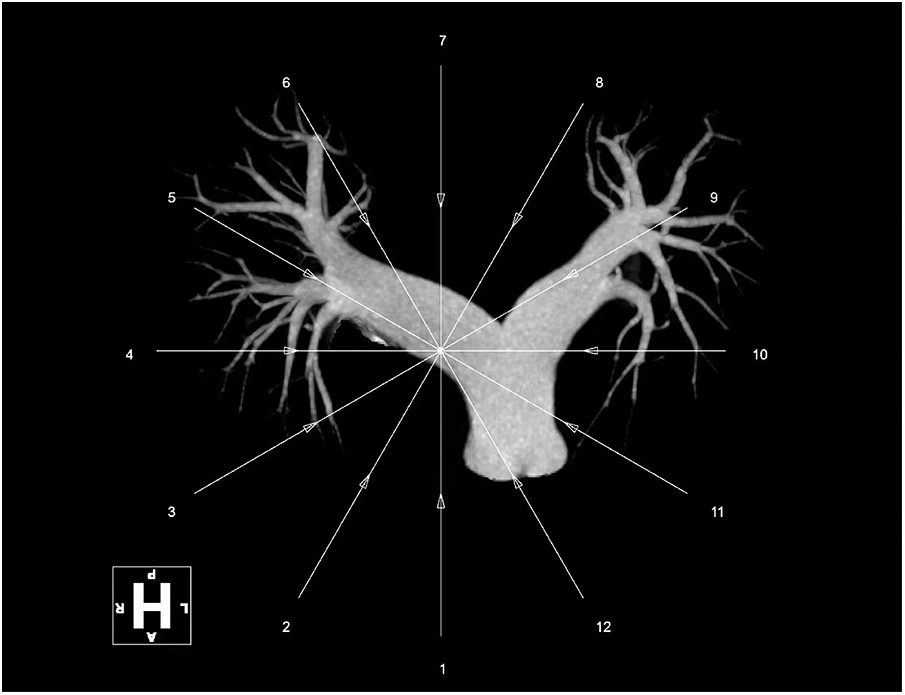

Over the next few hours after the procedure, the patient's oxygenation gradually increased to 99% on 2 L oxygen, hemodynamic status was restored to 122/66 mmHg on significantly reduced norepinephrine and a sinus rhythm (73 beats/min) was observed. The severe dyspnea was conspicuously alleviated, and tachypnea was resolved to normal status (19 breaths/min). Five days after the thrombus aspiration and in situ thrombolysis through the Guidezilla GEC, the patient's clinical condition was further improved and she was finally discharged to continue her rehabilitation. A new CTPA, scheduled for 2 months later, demonstrated a significant reduction in the size of the thrombus, which was barely visible (Figure 4).

Figure 4

3D reconstruction of CTPA in 2 months later.